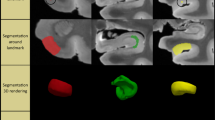

A growing number of studies have used in vivo structural MRI to derive measurements of subtle volumetric changes in the MTL caused by neurodegeneration [11, 24]. Most recently, Wisse et al. conducted a postmortem study which investigated the association between the thickness of MTL subregions in ex vivo MRI and semi-quantitative ratings of different neurodegenerative pathologies derived from histology samples taken from the contralateral hemisphere [ Brain hemispheres were obtained from twenty-nine donors; one specimen from the brain bank operated by the National Disease Research Interchange (NDRI), sixteen specimens from autopsies performed at the University of Pennsylvania Center for Neurodegenerative Disease Research (CNDR) and twelve specimens from the University of Castilla-La Mancha (UCLM) Human Neuroanatomy Laboratory (HNL) in Spain. Human brain specimens were obtained in accordance with the University of Pennsylvania Institutional Review Board guidelines, and the Ethical Committee of UCLM. Where possible, pre-consent during life and, in all cases, next-of-kin consent at death was given. CNDR hemispheres were fixed in 10% formalin solution for at least 30 days before extracting intact MTL blocks. HNL cases were fixed by perfusion with 4% paraformaldehyde through both carotid arteries. The blocks were then imaged on a Varian 9.4 T animal scanner at a 200 × 200 × 200 µm3 resolution. Details of the imaging protocol are provided in Additional file 1: Section 1.1 and Additional file 1: Fig. S7. Following MRI scanning, each of the specimens underwent histological processing for neuropathological examination and neuroanatomical analysis. In twenty-seven specimens, dense serial histology was performed. The specimens were cut into 2 cm blocks using custom molds that were 3D printed to fit each MTL specimen, cryoprotected and sectioned at 50 μm intervals in a sliding microtome coupled to a freezing unit (Microm, Heidelberg). For neuropathological diagnosis, we were interested in examining the anterior ERC at the mid-level of the amygdala, and the dentate gyrus (DG) and CA subfields at the mid-level of the body of the hippocampus. Therefore, for the remaining two specimens that did not undergo serial histology, two tissue blocks were cut at the level of the amygdala and hippocampal body, cryoprotected and sectioned into 50 μm sections. For each of the specimens, two adjacent sections were sampled at the mid-level of the amygdala and the hippocampal body for immunohistochemistry. In each case, the two sections were immunostained for tau and TDP-43 using anti-human PHF-Tau (monoclonal antibody (mAb), mouse, Thermo Scientific, Product Number MN1020, 1:500) and 66318-1-Ig Anti-phospho (409/410) TDP-43 (mAb, mouse, Proteintech, 1:350) respectively. Sections were then mounted on 7.5 cm × 5 cm slides and digitally scanned at 20× resolution. Regional thickness analysis was performed using histopathology ratings of tau and TDP-43 pathologies derived from the MTL both ipsilateral and contralateral to the one that was scanned. Semi-quantitative ratings for tau and TDP-43 pathology were obtained for the contralateral hemisphere by obtaining tissue samples at the time of autopsy and are available for a subset of twenty-eight donors (CNDR and HNL specimens) in three MTL regions routinely examined in the CNDR neuropathology evaluations [29]. For each of the specimens, the boundaries between MTL subregions cornu ammonis (CA) 1, CA2, CA3, DG, SUB, presubiculum, parasubiculum, hippocampal amygdala transition area (HATA), SRLM, ERC, BA35, BA36, area TE and the parahippocampal cortex (areas TF and TH) were identified on the basis of cytoarchitectural features in the Nissl stained sections following the anatomical rules presented in the Atlas of the Human Brain by Mai et al. [30]. Annotations were performed on each histology slice by the team of neuroanatomists at UCLM (the hippocampal subfields and ERC were annotated by M.M.A, E.A.P, M.M.R, M.M.L, C.R.P, S.C.S, J.C.D, M.C.P and F.M.R., supervised by R.In; R.In annotated the boundaries of the temporopolar cortex, PRC and PHC, and revised the annotations of the group). The neuroanatomists viewed scanned Nissl slides in an open-source web-based system (https://github.com/pyushkevich/histoannot) and used line drawings and text labels to annotate boundaries between adjacent anatomical regions. Following histology reconstruction and registration to MRI, the boundary annotations were overlaid on the co-registered MRI and histology images. Additionally, the manual segmentations of the whole MTL cortex and SRLM that were used to guide groupwise registration were registered to the histology images to inform the outer MTL boundary. The MRI, histology and MTL segmentation images were displayed side-by-side in ITK-SNAP [31] to facilitate manual tracing of the subfield segmentations in 3D MRI space, which was performed by S.L. with supervision from L.E.M.W and R.In (Additional file 1: Fig. S9). For each of the eleven specimens, the completed segmentations were then mapped to the MRI atlas using the deformable transformations generated by the groupwise registration pipeline. Note that for each specimen, small gaps in the segmentation may exist between blocks. A consensus segmentation of the MRI atlas was obtained by application of voxel-wise majority voting among the eleven segmentations with slight regularization by a Markov Random Field prior. More details on this approach are provided in the supplemental information, Section S1.4.5 of Adler et al. [1: Section 1.4). To test the effects of tau pathology on regional thickness, we fit a general linear model (GLM) at each vertex on both the MTL and SRLM surfaces with the average rating of tau pathology as the independent variable, thickness as the dependent variable, and age and TDP-43 rating as covariates. More details on the statistical analysis are provided in Additional file 1: Section 1.5. The specimens included in this study contain varying neuropathological diagnoses, including AD neuropathologic change and neuropathological diagnoses such as argyrophilic grain disease (AGD), frontotemporal lobar degeneration (FTLD) with TDP-43 inclusions, cerebrovascular disease and Lewy body disease. Figure 1 summarizes the demographic and neuropathology data for this brain donor cohort. The average ipsilateral tau and TDP-43 ratings across the twenty-nine specimens are 1.50 ± 0.97 and 0.54 ± 0.82 respectively. The average age is 74 years (range 44–93 years). Additional file 1: Table S2 provides more detailed demographic data and pathology information for each specimen. Demographic and diagnostic summaries for the twenty-nine brain donors. The tau and TDP-43 pathology ratings refer to the average rating computed from measurements sampled at three medial temporal lobe locations (entorhinal cortex at the mid-level of the amygdala and subiculum/cornu ammonis and dentate gyrus at the mid-level of the hippocampus). Dashed lines are used to indicate the mean value across specimens Figure 2 shows the MRI atlas of the MTL constructed from twenty-nine ex vivo specimens as a synthetic “average” MR image and a consensus MTL subregion segmentation derived from serial histology in eleven specimens. The atlas construction pipeline achieves excellent groupwise alignment between ex vivo MRI scans and captures the average shape of the MTL (Additional file 1: Section 2.1, Additional file 1: Fig. S2, Additional file 1: Fig. S3 and Additional file 1: Fig. S4). Following groupwise registration, each specimen has a pointwise spatial correspondence to this atlas. This correspondence is limited to the region of the MTL cortex which was semi-automatically segmented in each specimen. Figure 3 provides a visualization of the quality of the registration between individual specimen images and the final atlas. In some specimens, the PRC, which includes BA35, was particularly challenging to register due to significant anatomical variability in cortical folding and branching patterns [32, 33]. Overall, the warped specimens look similar to each other following registration, although some minor mis-registrations remain. Quantitative and visual evaluation of atlas quality at different stages of atlas construction, and comparisons with an alternative atlas-building strategy are presented in Additional file 1: Section 2.1. Computational atlas of the medial temporal lobe (MTL) constructed by groupwise registration of the magnetic resonance image (MRI) scans of twenty-nine ex vivo specimens. Three coronal sections are shown ordered from anterior (ant) to posterior (post), indicated as I, II and III, as well as a sagittal and axial section through the MTL. For each section, the “average” MRI is shown with and without the consensus MTL subregion segmentation derived from serial histology in eleven specimens. In the top right, a 3D reconstruction of the MTL atlas is shown along with a 3D brain rendering indicating the location of the MTL within the brain. (med medial, lat lateral, sup superior, inf inferior, SUB subiculum, SRLM stratum radiatum lacunosum moleculare, CA cornu ammonis, DG dentate gyrus, HATA hippocampal amygdala transition area, ERC entorhinal cortex, BA Brodmann Area) Coronal view of the MRI scans of each of the twenty-nine specimens warped into the space of the MRI atlas. The corresponding atlas image is outlined in blue, in the bottom-right corner. The more similar the warped images are, the better the atlas quality. The dashed blue circles point out examples where the perirhinal cortex (region surrounding the collateral sulcus) was particularly challenging to register due to significant variability in cortical folding patterns. The color bar at the bottom of each image indicates the average neurofibrillary tangle (NFT) rating for that specimen. Yellow represents a rating of 0 (no/rare pathology) and red represents a rating of 3 (severe Alzheimer’s disease) Figure 4 shows the results of the pointwise thickness analysis performed on the MTL and SRLM examining the regional effects of tau pathology on cortical thickness using pathology ratings derived from the MTL ipsilateral to the thickness measures. Cases CNDR12 (44 y.o.) and HNL01 (45 y.o.) were excluded from the thickness analyses since these younger cases are outliers in terms of age and including them skews age effects, thereby dampening the associations between pathology and thickness. In this work we only consider the effects of tau and TDP-43 pathology on MTL structure since recent work studying the contribution of mixed pathology to MTL atrophy in AD showed no clear relationship between neurodegeneration and either Aβ or \(\alpha\)-synuclein [34, 9, 29]. These NFT density maps are generated using a weakly supervised deep learning algorithm, trained to specifically detect tangles and pre-tangles on AT8-stained sections and have been shown to correlate strongly with manual NFT counts [29]. Three cases with a primary FTLD-Tau or AGD diagnosis (CNDR01, CNDR06 and CNDR07) were excluded from the analysis since they likely contain 4R-tau inclusions which can be difficult to distinguish from AD-related NFTs. In the remaining twelve cases, we examined the correlation between the average NFT burden computed within each hotspot and the median thickness of each hotspot, and observe very strong correlations, although the hotspot in the ERC does not reach significance (Additional file 1: Fig. S12). These results are weakened when we include age in the model. This is likely due to the small sample size and the fact that age and tau are significantly correlated (average R = 0.61 across the three hotspots). Despite the small dataset, these results are encouraging and suggest that NFTs are indeed playing a role in driving neurodegeneration in the ERC, SUB and SRLM hotspots. As we expand our dataset, collect more quantitative histology data and develop automated methods to extract quantitative measures of the different types of tau and TDP-43 pathology, in future work we will be able to better overcome the above-mentioned limitations and validate the relationship between NFTs and thickness. Overall, our findings provide a more refined understanding of how tau pathology is associated with cortical thinning within the MTL and motivate further characterization of the MTL in AD using detailed ex vivo MRI analysis. The clusters identified from the tau thickness analyses indicate granular MTL regions where in vivo measures of neurodegeneration are expected to be strongly associated with tau pathology. In an exploratory analysis, we attempted to use the ex vivo derived, AD-specific hotspots (Fig. 4B) as biomarkers in a longitudinal analysis of ADNI data (not shown). While the hotspots did not show statistical effects in a group comparison of Aβ negative, tau negative (A−T−) and Aβ positive, tau positive (A+T+) patient groups with mild cognitive impairment, BA35 achieved the strongest group discrimination. The lack of statistically significant group differences with the hotspots may be due to the small ex vivo sample size, clinical heterogeneity in our dataset and difficulties in accurately aligning BA35 in the atlas. Constructing a probabilistic atlas of the MTL has far-reaching applications in AD research beyond the work shown here. Perhaps future analyses leveraging this technology in a patient cohort more consistent with the one we would expect to encounter in an AD clinical trial would result in hotspots that are more sensitive to longitudinal change in the presence of NFT pathology, potentially enabling the development of neurodegeneration biomarkers which are more effective during early AD clinical trials. Furthermore, in future work, 3D quantitative maps of NFT density derived from serial histology imaging will be mapped into ex vivo atlas space to generate a comprehensive probabilistic description of the progression of NFT pathology at each Braak stage [29, 48, 49]. This will allow us to describe NFT topography during the different stages of AD in more detail than current descriptions, which are in 2D and based on selective sampling of the MTL [1, 2]. Additionally, in a future version of the atlas, cytoarchitecture-guided anatomical labels of MTL subregions will be included from a larger number of specimens. Such an atlas would reflect anatomical ground truth and can be used to inform in vivo MRI protocols for segmentation of MTL subregions, thereby improving the accuracy of MRI biomarkers derived from these subregions.Methods